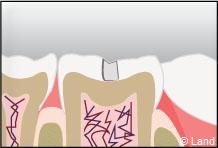

L’inlay-onlay reconstituera la dent comme la dernière pièce d’un puzzle. Il sera véritablement collé dans la dent.

Il aura un rendu naturel et présentera une meilleure étanchéité assurée par le collage, il sera aussi plus durable que d’autres types de reconstitutions dites foulées.

Exemple d’un onlay molaire